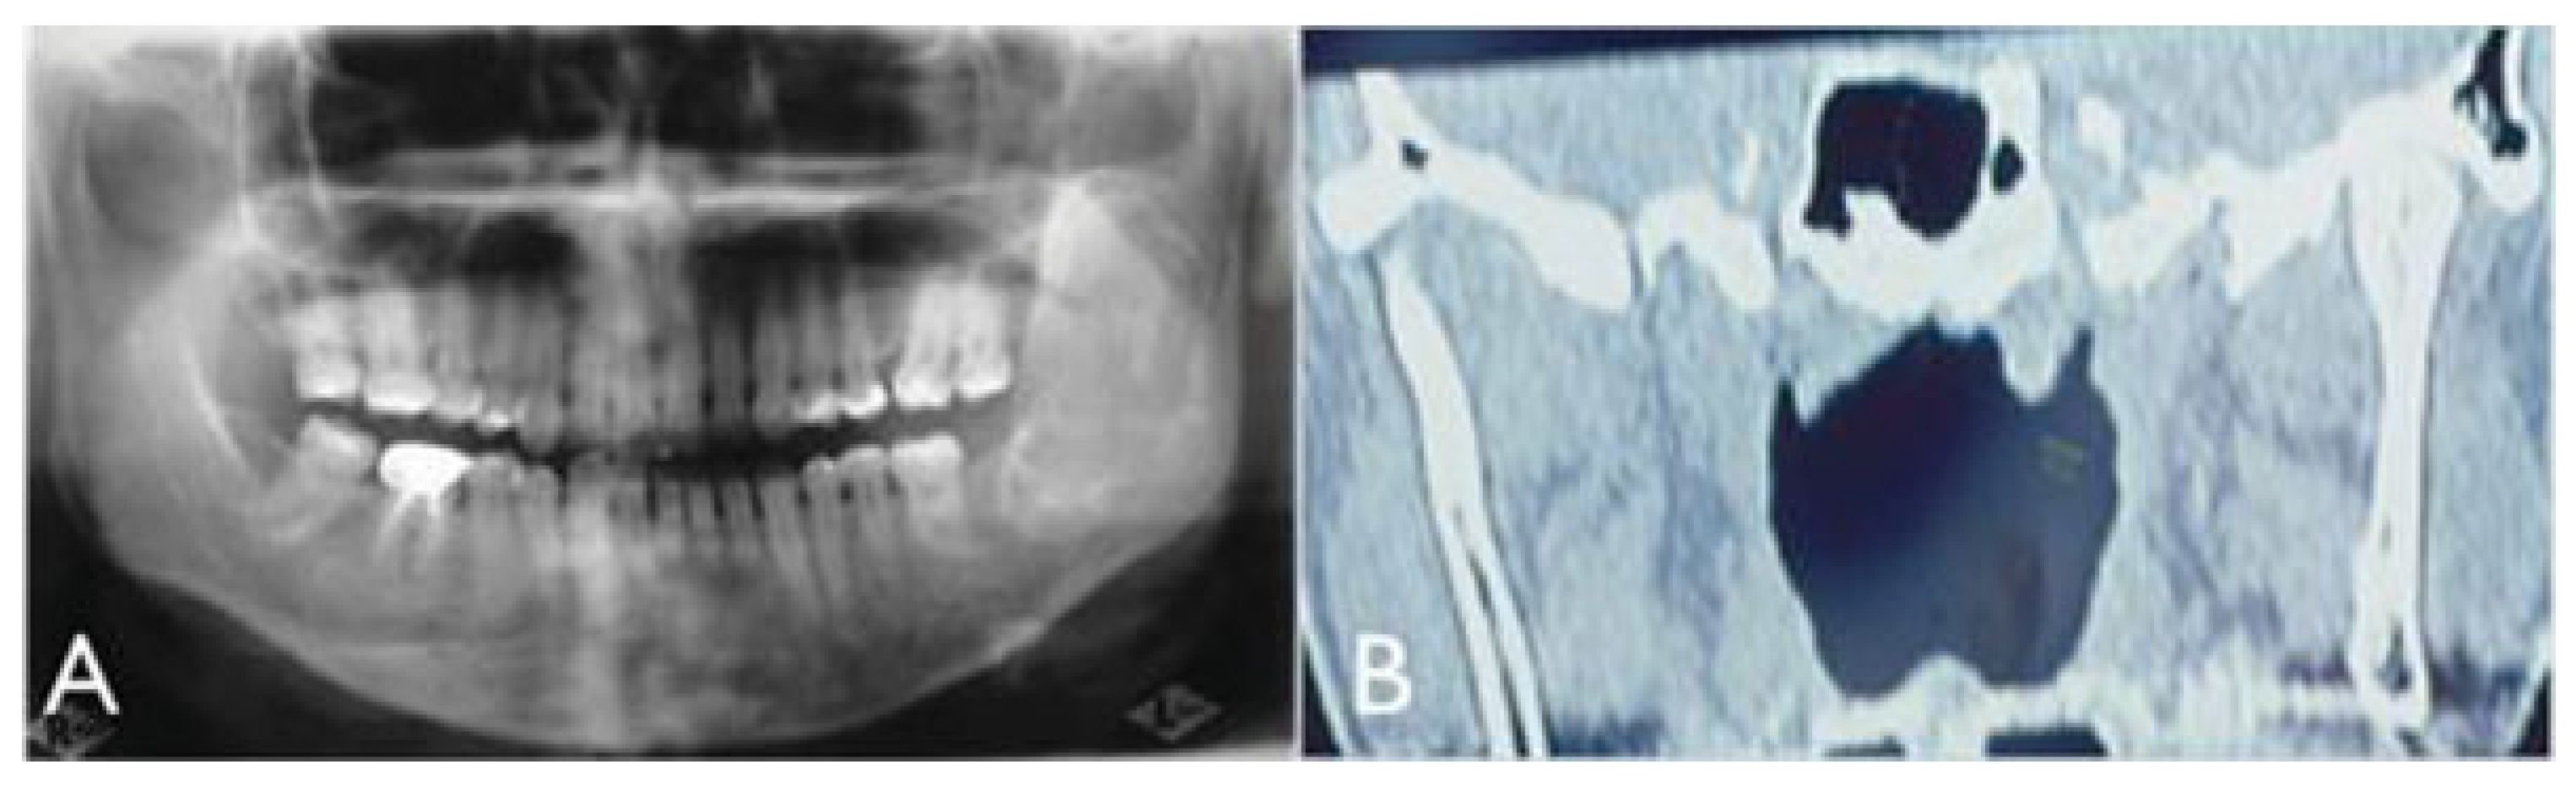

Figure 3. (A) Panoramic radiograph showing neoplasia in left mandibular body and ramus. (B) Axial computed tomography showing idiopathic condylar resorption of the right condyle.